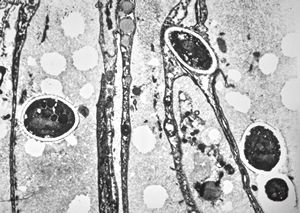

M, 28y. | leishmaniosis … skin of the cheek

M, 28y. | leishmaniosis … skin of the cheek